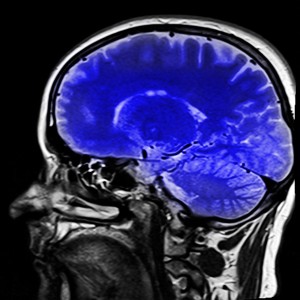

Sie sind hier: Startseite Nachrichten Gesundheit Ultraschall verringert Parkinson-Symptome Gehirn: Ultraschall erlaubt gezielte Behandlung von Parkinson.

Gehirn: Ultraschall erlaubt gezielte Behandlung von Parkinson.

Foto: pixabay.com, kalhh